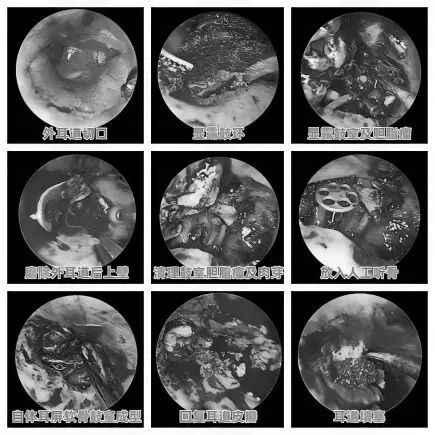

耳朵反复流脓、听力下降还有异味?当心,这可能是慢性化脓性中耳炎的症状。由于早期症状时好时坏,很多人觉得不是大问题,但拖延不治可能对听力造成不可逆的损伤。今天我们就来认清它的真面目,学会如何科学应对。 什么是“慢性化脓性中耳炎”? 慢性化脓性中耳炎,俗称“灌耳心”,典型症状包括耳内反复流脓(常为脓性分泌物,严重时可伴有臭味)、听力下降以及耳鸣等,部分患者还可能伴有眩晕。很多人是从小时候就开始出现症状,尤其是耳朵进水后容易急性发作或加重,成年后,听力持续减退往往成为主要困扰。 如果不及时治疗,炎症可能“向上”蔓延到颅内,引发脑膜炎、脑脓肿等危及生命的严重并发症。也可能侵犯面部神经或平衡器官,导致面瘫、持续眩晕或平衡障碍。最直接的后果是听力会不可逆地下降,严重时可能导致完全失聪。 “慢性化脓性中耳炎” 如何治疗? 慢性化脓性中耳炎的基础治疗需先用双氧水或生理盐水清洗耳道脓液,再滴入敏感抗生素耳液(如氧氟沙星滴耳液)。急性发作或重症时需口服或静脉注射抗生素并辅以抗炎药。若药物控制不佳或已有器质性病变,则需手术,包括乳突切除术清除病变组、鼓膜成形术修复穿孔鼓膜、听骨链重建术改善传音功能及胆脂瘤清除术清除胆脂等。 患者常见问题解答 问 手术后多久能恢复听力? 答 术后恢复情况与手术方式、个人身体情况有关。若为鼓膜修补手术,术后1—3个月左右,听力会逐渐改善,若进行听骨链重建手术,通常需要 3 到 6 个月,听力才能趋于稳定。术后需定期复查,监测听力恢复情况。 问 儿童患者能手术吗? 答 如果孩子的病情确实需要手术,家长不用太担心,儿童也是可以接受手术治疗的。医生会根据孩子的年龄大小、病情严重程度,选择最适合的手术方式,比如现在常用的微创技术,就能尽量减少手术对孩子耳朵的创伤,让孩子恢复的更好。 问 如何预防复发? 答 术后严格遵医嘱用药、复查,避免感冒及耳部进水,保持鼻腔通畅,减少咽鼓管阻塞。 贵州航天医院耳鼻咽喉科简介 张光进 中共党员,耳鼻咽喉科主任,副主任医师 临床擅长:对耳鼻喉头颈常见病的诊治具有丰富的临床经验,擅长鼻内镜、耳内镜、耳显微、头颈咽喉部肿瘤及眩晕手法复位等的诊疗。 曾先后前往第三军医大学西南医院、复旦大学耳鼻喉科医院、上海新华医院及北京友谊医院进修学习;遵义市医学会常务委员;主持及参与级科研课题2项,发表专业论文10余篇。 陈维信 九三学社社员,耳鼻咽喉科主任医师 临床擅长:对耳鼻咽喉科常见疾病的诊治具有丰富的临床经验,擅长耳、鼻、喉及头颈部位的手术。 曾先后前往上海交通大学附属仁济医院耳鼻喉-头颈外科、北京大学人民医院耳鼻喉-头颈外科参加鼻内镜外科进修学习。中国睡眠研究会委员,贵州省医学会耳鼻喉-头颈外科学分会委员,贵州省耳鼻喉-头颈外科学会理事,贵州省医学会变态反应学分会委员,贵州省防聋治聋技术指导组专家,遵义市耳鼻喉科分会副主任委员,遵义市医疗事故鉴定专家库成员;主持省部级科研课题2项,发表专业论文20余篇。 秦 晋 耳鼻咽喉科副主任医师 临床擅长:对耳鼻咽喉科常见疾病的诊治具有丰富的临床经验,擅长耳、鼻、喉及头颈部位的手术。 遵义市医学会常务委员;曾先后在第三军医大学西南医院、湖南湘雅鼻颅底培训班进修学习。 贵州航天医院耳鼻咽喉科简介 基本情况 贵州航天医院耳鼻咽喉科拥有一支经验丰富、技术精湛的医疗团队,共有医师9名,其中副高级以上专家5名,医学硕士2名,开放床位20张,拥有德国WOLF鼻窦内窥镜系统、日本奥林巴斯电子喉镜、奥林巴斯电子鼻咽镜、丹麦临床听力监测设备、声导抗仪、听觉诱发电位、耳声发射仪、美国杰西低温等离子治疗仪、杭州好克鼻窦内窥镜系统、鼻动力系统、耳显微镜、耳用电钻、微波治疗仪等设备。 专科特色 (一)耳部疾病 耳内镜下胆脂瘤切除术、III型鼓室成形术+人工听骨链重建术。 (二)鼻部疾病 内镜下鼻息肉切除术、鼻窦功能开放术。 (三)咽喉疾病 内镜下扁桃体、腺样体低温等离子切除术 (四)交叉学科 1.经鼻内镜下眶内肿瘤切除术 2.经鼻内镜下鼻腔泪囊吻合术 诊疗范围 (一)常见耳疾的诊断和治疗:中耳炎、耳聋、耳鸣等。通过各种耳科检查手段,如耳镜检查、听力测试和耳脑干听觉诱发电位检查等,准确诊断患者病情,制定个性化治疗方案。 (二)鼻炎、鼻窦炎、鼻出血等鼻科疾病的诊断和治疗:采用微创技术,如鼻内窥镜检查、低温等离子手术等,为患者提供有效的治疗方案。 (三)喉炎、声带息肉、声带白斑等喉科疾病的诊断和治疗:通过声带电子镜、喉镜等设备,准确判断患者的喉部病变,为患者提供精准的治疗方案。 (四)鼻眼、鼻颅底相关手术。